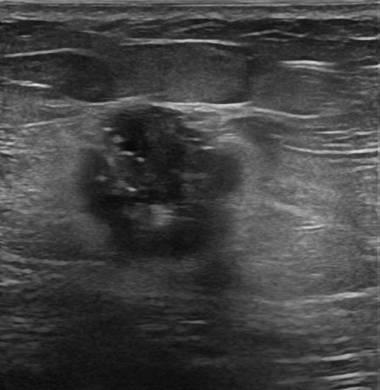

Ung thư vú

» Thông tin: Nữ giới – 51 tuổi.

» Lâm sàng: Khối tuyến vú.